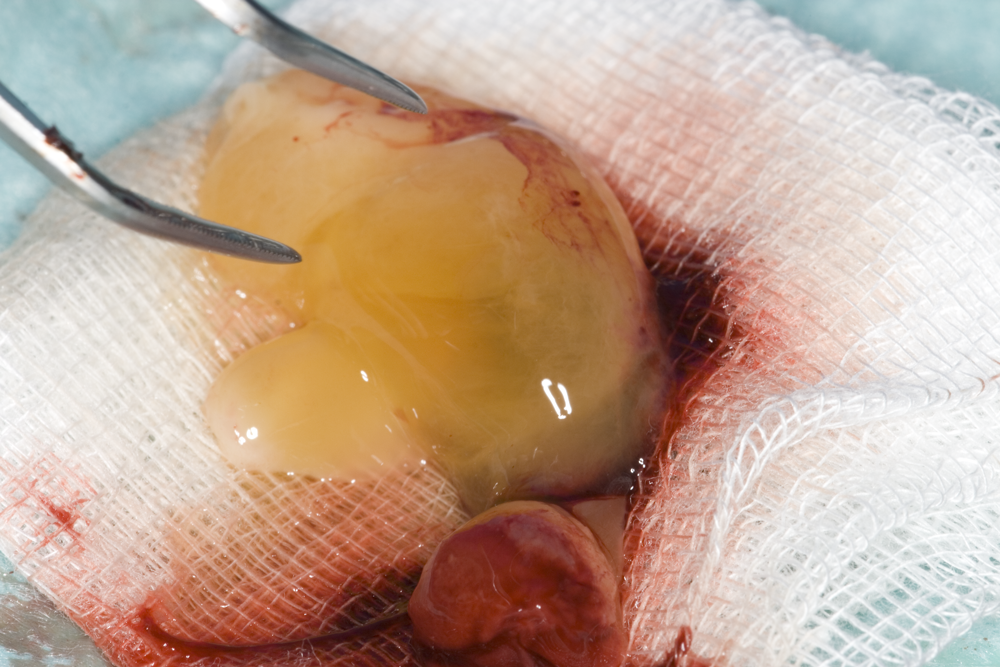

Автогенна кост

PRF